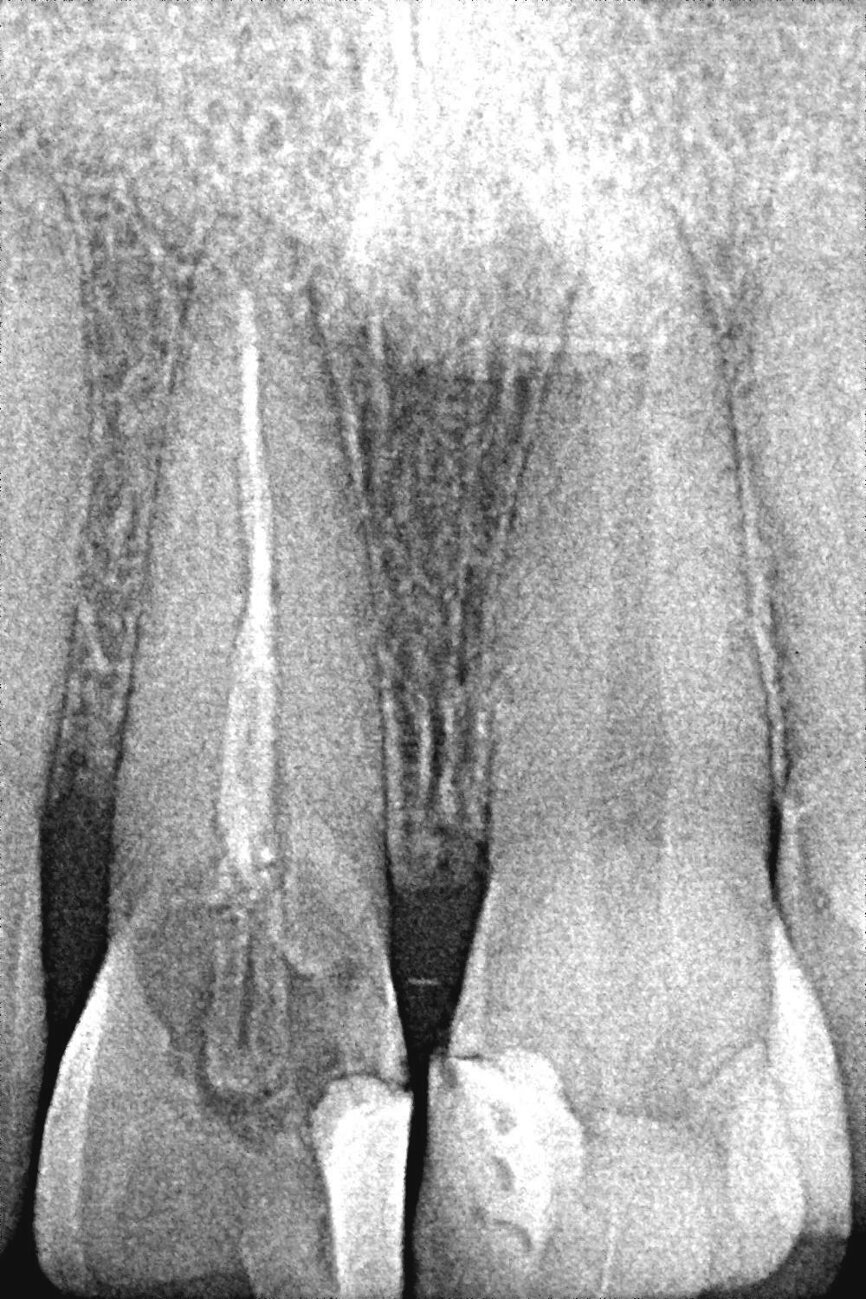

La patiente, âgée de 36 ans, nous a consulté pour un contrôle dentaire en raison d’une douleur dans la région des dents antérieures supérieures gauches. À ses dires, la douleur commençait subitement et s’aggravait lors de la mastication. L’examen clinique de l’incisive centrale supérieure gauche (dent 21) a révélé une inflammation, une douleur à la percussion et une fracture de la dent au niveau de la limite cervicale. La dent avait fait l’objet d’un traitement endodontique trois ans plus tôt et n’avait jamais été restaurée auparavant. Une radiographie a montré une couronne fracturée touchée par une résorption radiculaire mineure ainsi qu’une infection périapicale (Figs. 1a–c). L’examen radiographique comme l’examen clinique ont également confirmé la présence d’une largeur et d’une hauteur d’os suffisantes. Le pronostic très défavorable d’un retraitement endodontique a été expliqué à la patiente et elle a opté pour un traitement plus radical. La décision d’extraire la dent et de la remplacer immédiatement par un implant monobloc en zircone a donc été prise.

Fig. 1c : Radiographie de la dent 21.